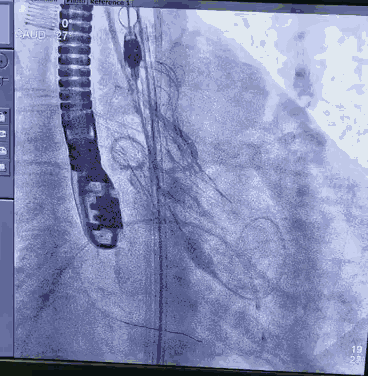

采用右股动脉为主入路,左股动脉为冠脉保护预留。先尝试干预PL慢性闭塞病变,XT-R导丝通过闭塞病变,在球囊锚定下,1.25球囊通过病变扩张。复查造影显示闭塞远端血管细小,放弃进一步干预右冠。

顺利跨瓣,测得跨瓣压差62mmHg。送20mm球囊扩张主动脉瓣,经右桡动脉猪尾导管造影,冠脉切线位未见右冠脉显影。为策安全,决定对RCA行冠脉保护,送JR4导管及guidzila和3.5球囊行冠脉保护。置入24mm微创 vitaflow瓣膜标准位释放。复查造影显示少量主动脉瓣返流,左右冠显示良好,撤除右冠保护。术后测压差为10mmHg。缝合双侧股动脉。术后恢复良好,次日转回普通病房,顺利出院。